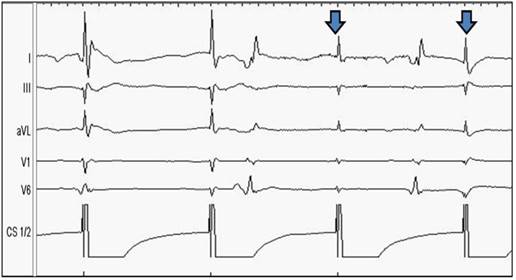

In addition to the described approach, we applied a further safety measure to prevent patients in the second ablation group from PNP from May 2012 onward (Arctic Front Advanced TM®). Therefore, during ablation of the RSPV and RIPV, the upper extremities lead I was newly adjusted between the inferior sternum and the right chest, thereby recording the maximum diaphragmatic compound motor action potential (Figure 2). Electrode left arm was placed 5 cm above the xyphoid process at the left margin of the inferior sternum, electrode right arm was placed on the xyphoid level in the right front axillary line. The amplitude of CMAP was continuously recorded on lead I and observed in a semi-quantitative manner during PVI in a beat-to beat-analysis (Figure 3). Interference with more of ≥30% ECG amplitude decrease or complete loss of the ECG amplitude led to an immediate interruption of the freeze. In the case of capture loss or interference of the ECG amplitude, PNS was continuously conducted until PN recovery could be observed. In the meantime, the current coronary sinus catheter position was compared with the original position, and when dislocated, readjusted to its original position if necessary.

Figure 3

Phrenic Nerve Stimulation without (A) and with (B) modified ECG-arrangement, the upper extremities lead I was newly adjusted between the inferior sternum and the right chest, thereby recording the maximum diaphragmatic compound motor action potential (CMAP).

In the fairly larger Observation Group II (consisting of 105 patients), we observed only 4 patients with PNP (equaling 3.8% of Observation Group II, Figure 6). Due to the ECG conduction modified in comparison to the conventional Study Group I, the amplitude of the QRS in lead I could be easily observed, as demonstrated in Figure 3, 4 and 5. During ablation of the RSPV and RIPV, the ECG-amplitude was continuously observed and semi-quantitatively assessed in a beat-to-beat analysis. As can be seen in Figure 5, a reduction of more than 50% of the amplitude could be noticed prior to the loss of contractility, indicating an infringement of the phrenic nerve. The immediate interruption of the freeze led to a significant reduction in PN disturbance. Those patients sustaining PN injury with this technique recovered immediately, subsequently demonstrating rapid growth in the ECG amplitude. Ongoing PNP was not observed in this study group. Typically, the reduction of ECG amplitude occurred prior to the loss of diaphragm contractility hereby proving itself as a more sensitive observation tool for CB ablation techniques.

Figure 5

Prior to the loss of contractility, a slight decrease of ECG-amplitude can be noticed; the contractility of the diaphragm is still preserved at this point. From the top to the bottom: Surface ECG leads: I, II, aVL, V1, V6. Endo-cardiac signals: Coronary sinus CS 1/2.